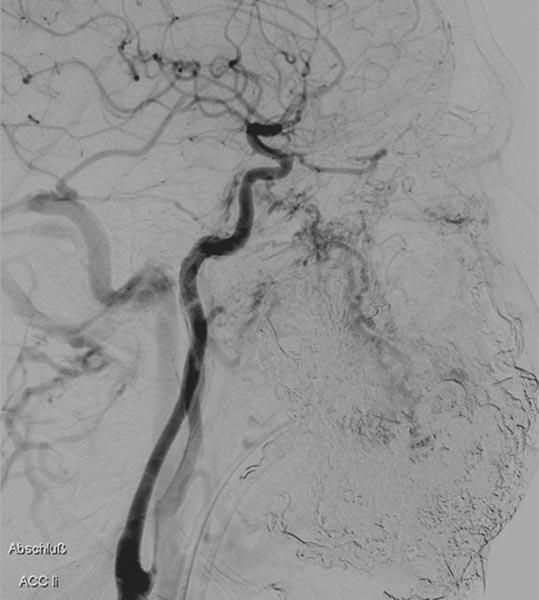

Late phase of DSA (lateral view) via the left internal carotid artery. After successful multiple embolizations, the supply to the nidus of the AVM via these critical branches is also occluded and the ophthalmic artery is preserved.